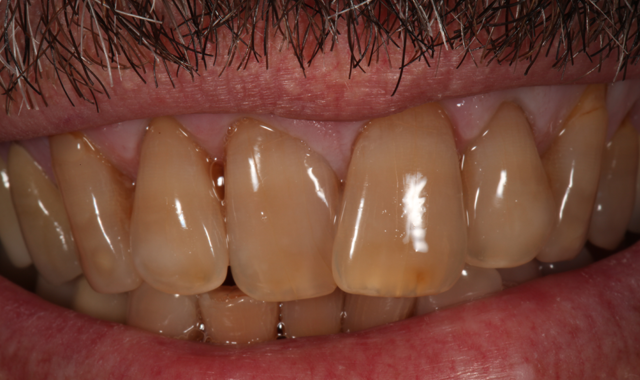

Fig. 1

Fig. 2

A male patient in his mid-60s presented with a chief complaint about the esthetics of his anterior maxillary and mandibular teeth (crowding, severe tetracycline staining) (Figs. 1 and 2). Orthodontic treatment was suggested. However, because the patient had fairly significant sleep apnea requiring nighttime wear of a custom-molded device, he declined this option.